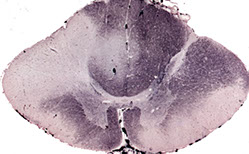

Subacute Combined Degeneration of the Spinal Cord

SCDSC with degeneration of white matter in posterior and lateral funiculi of the spinal cord. The degenerated fibers lose their myelin and are thus unstained